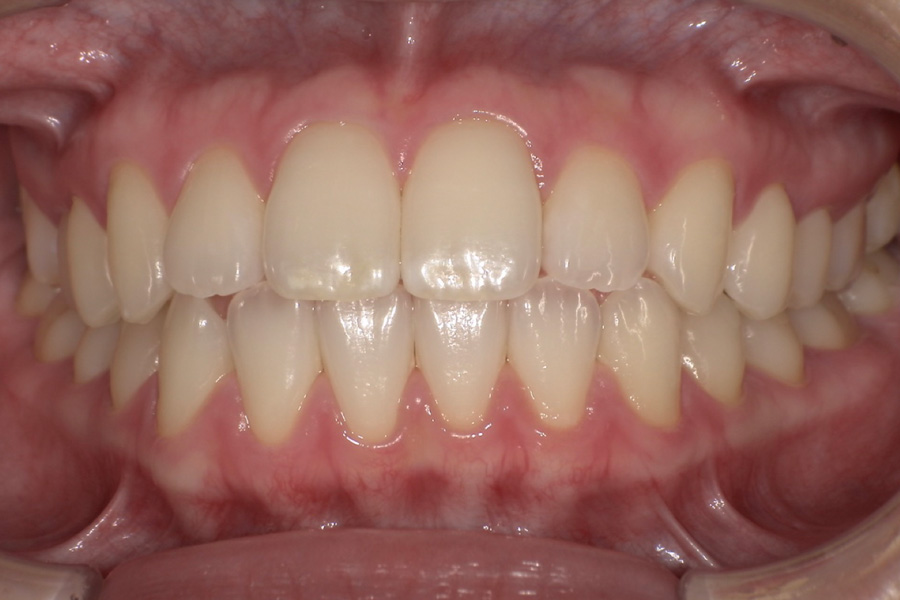

虫歯があるから削ったり悪くなったから抜くのではなく、まずは虫歯と歯周病が起きないようにより良い環境づくりをすること、そうすることによって歯を長く維持することが可能となります。

そのためには、健康状態に関する情報と生活習慣などの状況を把握したうえで、お口の中のリスク評価をおこないます。

その結果をもとに、お一人お一人にあった治療計画をご提案させていただきます。

ご自分の歯で食べ、話し、笑える幸せを生涯にわたり維持するためのお手伝いを全力でさせていただきます。